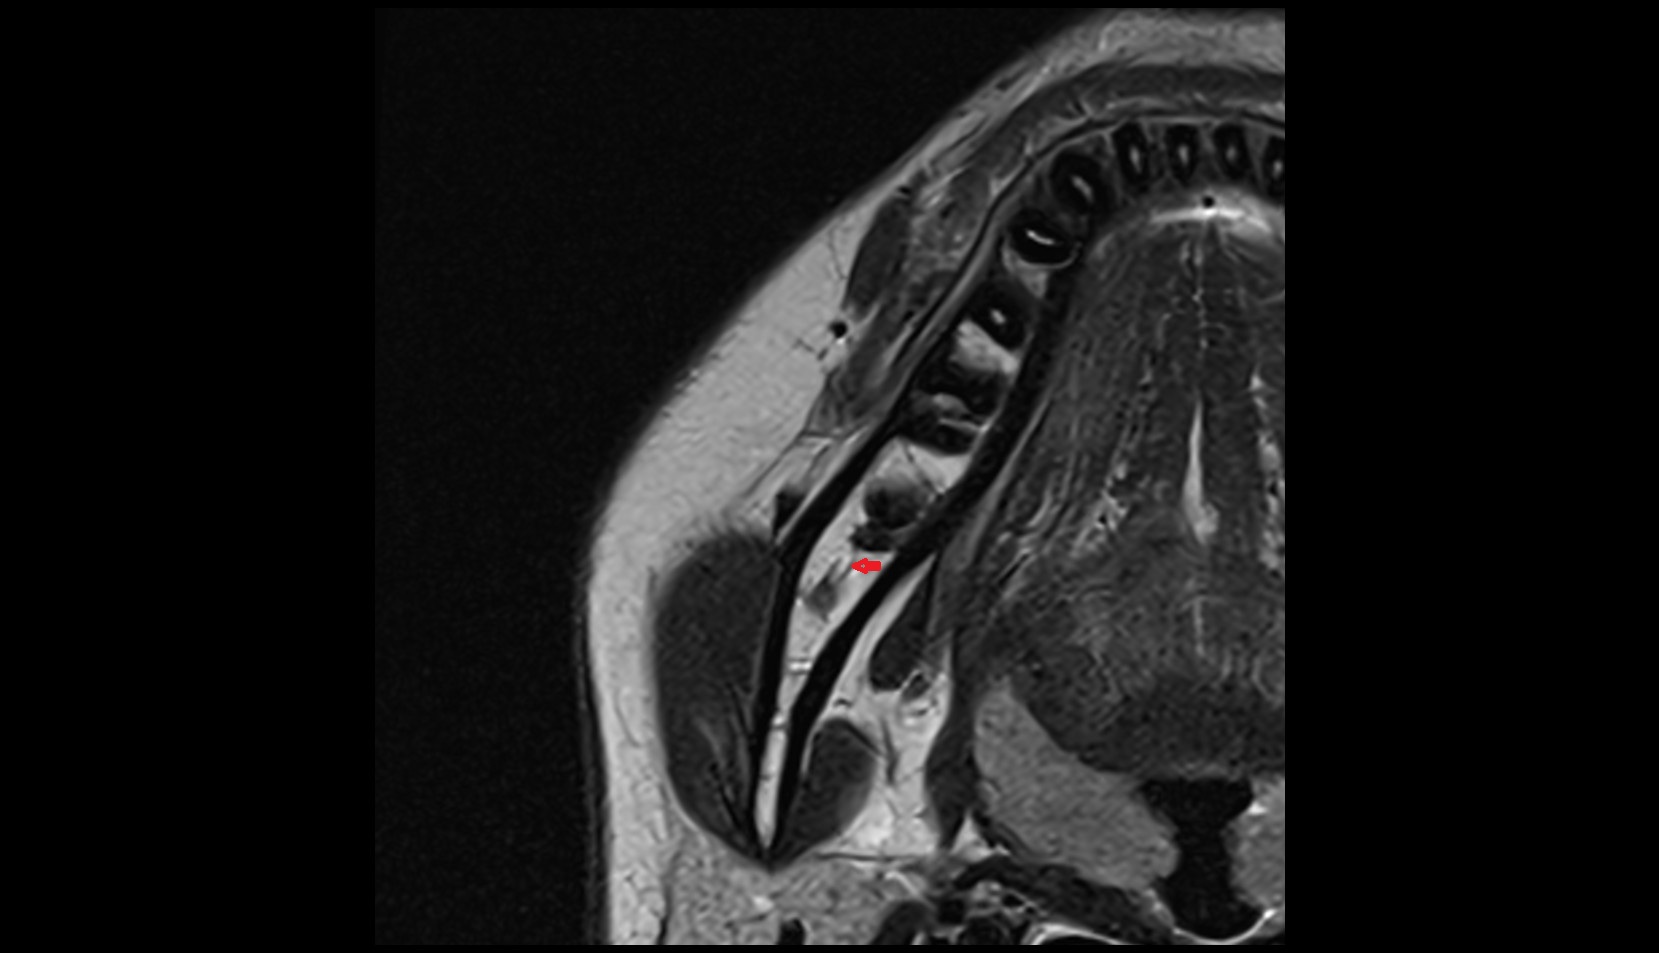

- Uterus

- Body of uterus

- Fundus of uterus

- Cervix of uterus

- Isthmus of uterus

- Vagina

- Fornix of the vagina

- Endometrium of uterus

- Myometrium of uterus

- Perimetrium of uterus

- Junctional zone of uterus